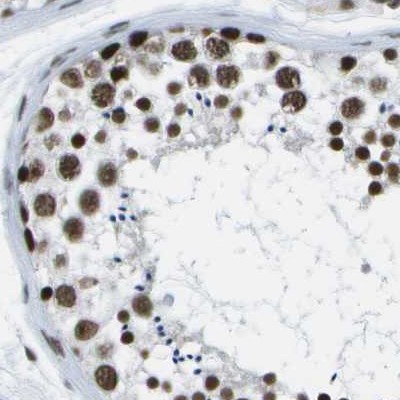

Immunohistochemical staining of human colon, kidney, lymph node and testis using Anti-NSRP1 antibody HPA015593 (A) shows similar protein distribution across tissues to independent antibody HPA015603 (B).